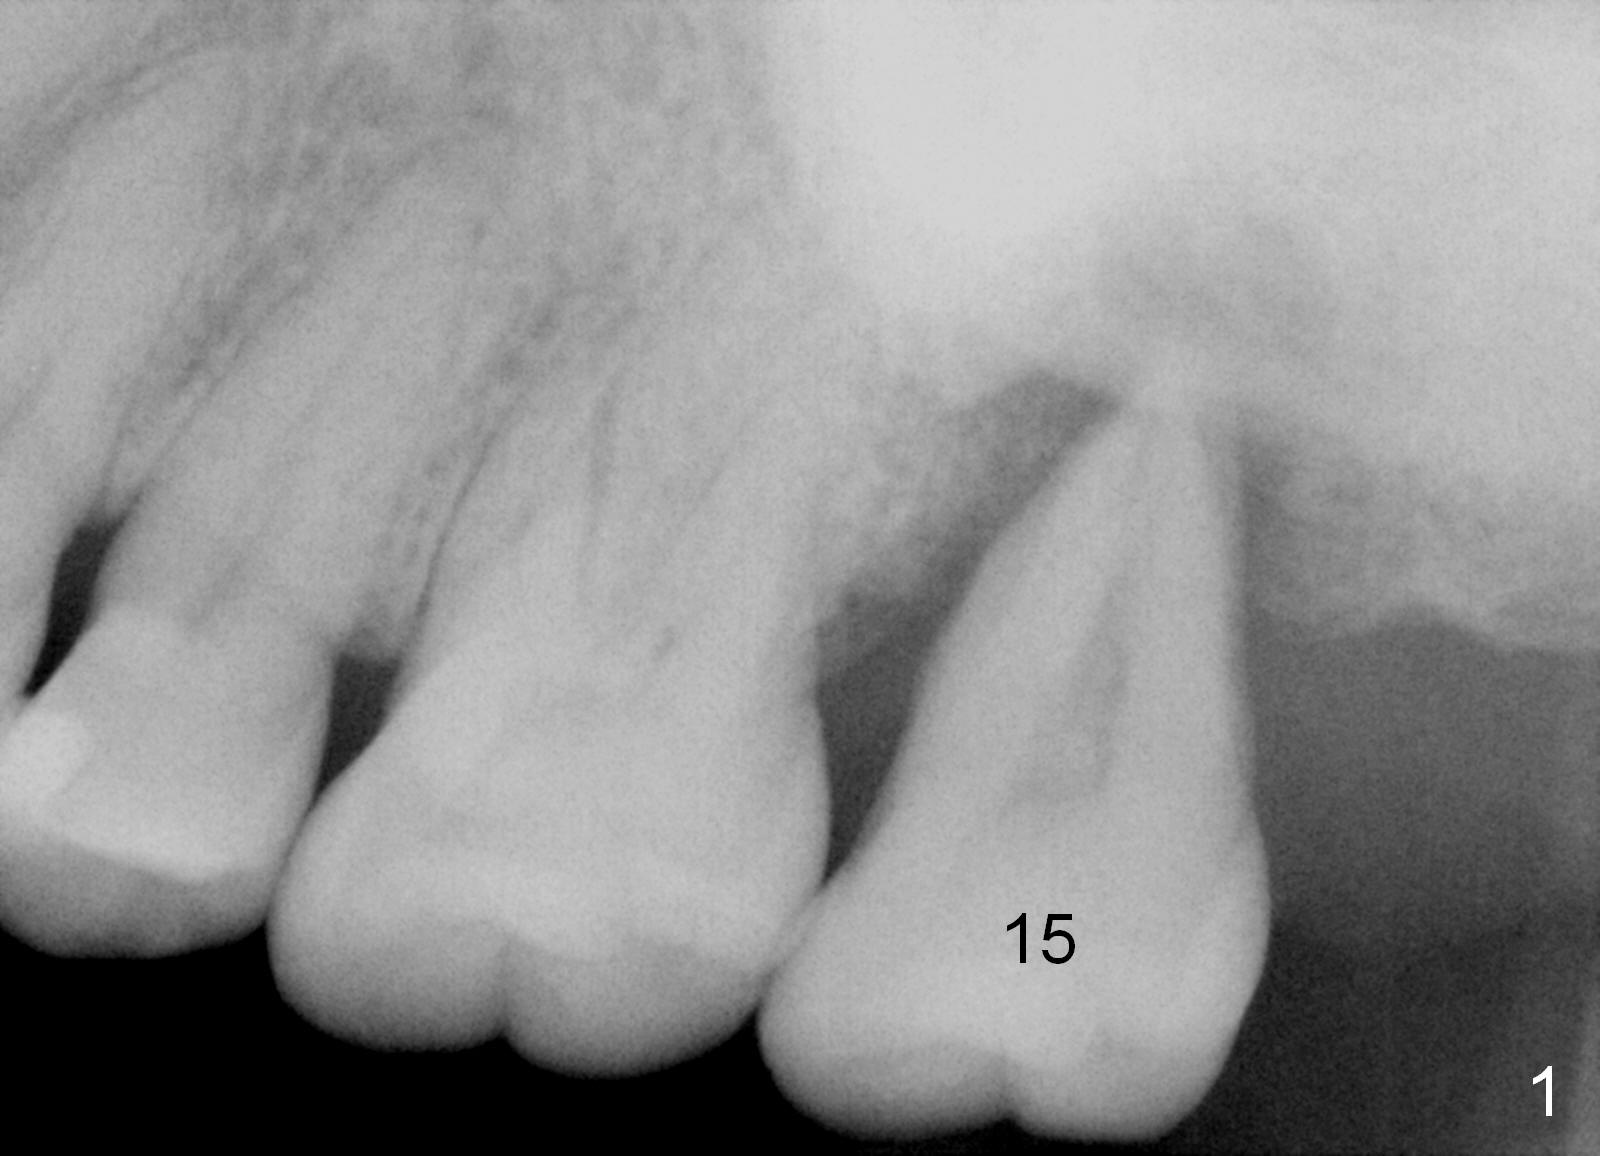

A 49-year-old lady has history of periodontal disease (Fig.1). The teeth #2 and 19 have been extracted and replaced by immediate implants. When she returns, crown is going to be cemented at #19 and delayed implant will be placed at #15. The tooth was extracted 4.5 years ago. No PA has been taken since extraction. Fig.2,3 show design for immediate implant if the tooth were not extracted (*: mesial crest; O: bone graft). Note the orientation of the implant and the space from the neighboring tooth.

#15 blade will be used for access and periosteal elevator for opening osteotomy site. Set implant spacer at 4 mm. Since the maxillary posterior region usually has poor bone density, bone expander kit will be most likely used until 2-3 sizes smaller than the expected implant. The latter will be decided by preop and intraop X-ray.